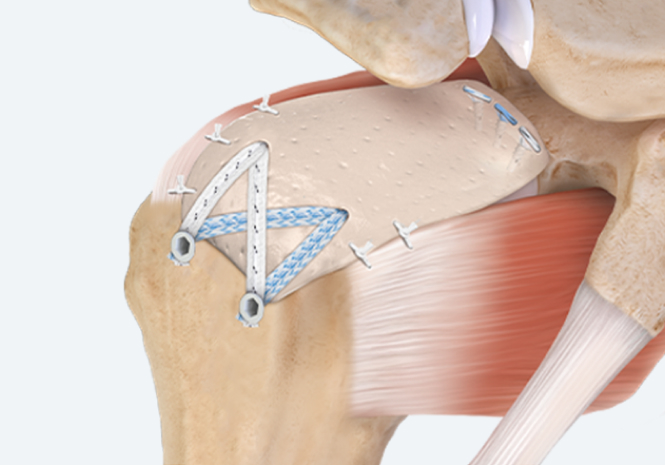

회전근개 패치 보강술은 파열된 힘줄을 잘라내지 않아 손상이 덜하며 무리하게 끊어진 힘줄을 당기지 않고 동종진피(acellular ermal matrix)를 이용해 끊어진 부위를 덮어 꿰매주는 시술로 재파열률을 현저히 줄인 선진수술법 입니다.

리제네텐 콜라겐 임플란트는 파열된 회전근개 부위에 콜라겐 패치를 덧대어 새로운 힘줄로 성장할 수 있게 지원하고 6개월 이내 점진적으로 흡수되어 새로운 힘줄과 같은 조직층으로 바뀝니다.

광범위 회전근개파열이 오래 지속되어 극상건이 찢겨 말려 올라갔을경우 필요한 치료법 입니다.

올라간 극상건 자리에 인공진피를 이용하여 상부 관절막을 재건해주는 이 치료법은 기술적으로 매우 복잡한 수술이므로

전문의의 노련함이 꼭 필요한 수술법 입니다.